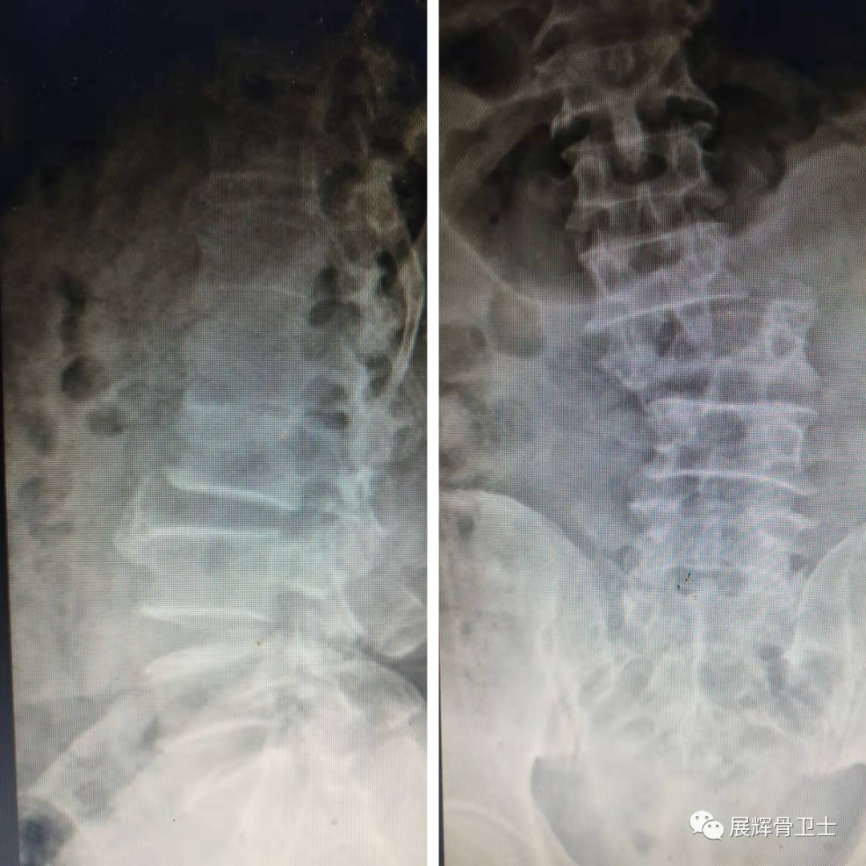

术前影像